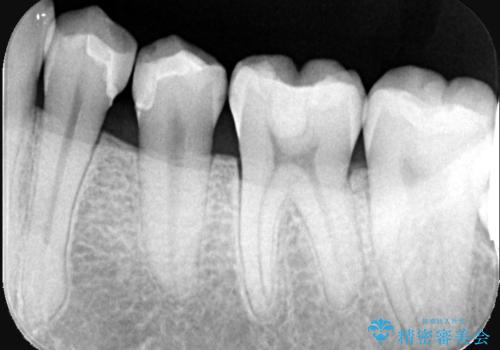

- 左下の第1・第2小臼歯の接触面にカリエスを認めました。

隣接面のため肉眼での確認が難しく、レントゲンにて診断を行ったのち、

マイクロスコープを使用して虫歯を丁寧に除去。

歯質の保存と適合精度、そして審美性を考慮し、セラミックインレーによる修復を行うこととしました。

マイクロスコープ下でう蝕検知液を併用し、感染歯質のみを丁寧に除去しました。その後、適切な形態に形成を行い、精密な印象採得を行ってセラミックインレーを製作しました。

装着時には拡大視野でインレーの適合を確認しながら、ラバーダムも使用して確実な接着操作を行いました。